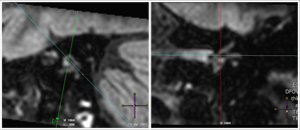

Internal acoustic canal Utricle Vestibule Lateral semicircular canal  Posterior semicircular canal

MRI imaging of the inner ear